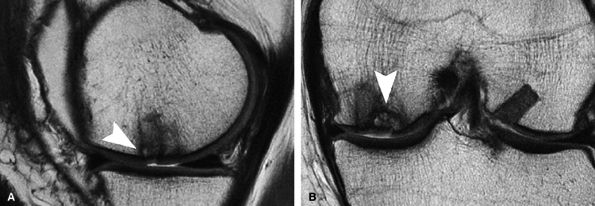

FIGURE 7.23 ● Sagittal inversion recovery (A) and axial fast spin-echo (B) MR images of the knee in a 31-year-old patient obtained 7 weeks following microfracture over the trochlea. Note the hyperintense reparative fibrocartilage over the defect (arrows). Sagittal fast spin-echo MR image (C) also demonstrates basilar delamination of cartilage without flap formation (arrowhead) adjacent to the area of microfracture, over the lateral margin of the trochlea.

|